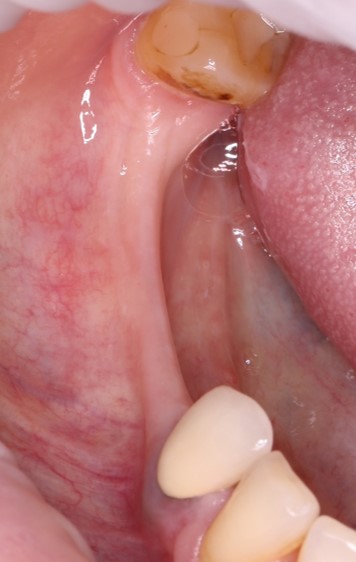

Другое дело, если у пациента в прошлом были частые обострения полириносинусита, есть вазомоторный ринит, а на КЛКТ мы обнаруживаем симптомы какой-то серьезной патологии: тотальное затемнение пазухи, большие по размеру полипы или кисты, инородные тела и т. д:

В этом случае, если не можем разобраться и справиться самостоятельно, лучше подключить к работе с пациентом опытного ЛОР-врача и действовать далее, исходя из его рекомендаций.